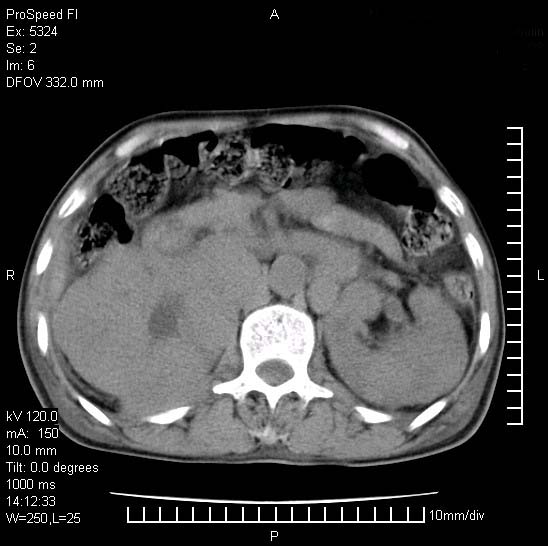

患者阴囊肿大14月,腰痛2个月,咳嗽,咳痰1周,患者现在肾功异常,做增强有些担心,我们用的是欧乃派克.

右侧肾癌伴腹膜后淋巴结转移!

右侧肾癌后腹膜转移,腹腔少量积液

腹膜后淋巴结肿大包饶腔静脉,双肾病变,建议增强

双肾均有软组织密度舯物,腹膜后淋巴结肿大包饶腔静脉------考虑为恶性占位病变,转移瘤可能。

左肾也有问题呀///

支持:双肾均见软组织密度肿块影,腹膜后淋巴结肿大包绕腔静脉------考虑为恶性占位病变,转移瘤可能。

1)考虑双肾恶性肿瘤(肾癌?)。2)腹膜后淋巴结肿大,多为肿瘤转移所致。

腹腔积液,双肾均有稍高密度肿块,主动脉旁广泛淋巴结肿大,融合,无显著肿块坏死征像,多考虑淋巴瘤累及双肾,不排除肾癌伴转移(肾癌这么大应该较多坏死了),另阴囊肿大,不知是实质肿大还是阴囊积液,如是是积液,多为腹腔肿块压近睾丸静脉所致,如是是实性的,多为淋巴瘤

1、淋巴瘤,双肾转移瘤;2、双侧肾癌,伴有腹膜后淋巴结转移。

双肾周围及腹膜后改变符合恶性病变,现在关键是要明确阴囊肿大的原因,是否为肿瘤性病变.如阴囊为恶性肿瘤那一切用转移即可解释,如阴囊为水肿改变,那需重新分析检查明确.

双肾均有软组织肿块伴腹膜后淋巴结肿大融合,右侧结肠旁沟积液;考虑恶性肿瘤。转移瘤?淋巴瘤?

阴囊肿大是实质性的么,为什么不扫阴囊,此扫描做的是什么部位,肾脏没包括全,也可以考虑生殖系统肿瘤转移

双肾增大,腹膜后多发肿大淋巴结影.首先考虑淋巴瘤.

双肾增大,结合腹膜后淋巴结肿大,考虑双肾恶性肿瘤并转移可能。

双肾癌并腹膜后淋巴结转移

考虑恶性淋巴瘤侵及双肾,腹膜后淋巴结肿大。